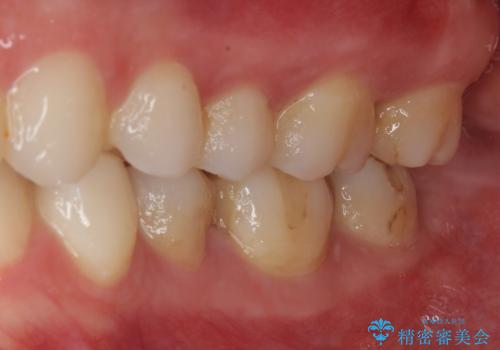

- 大学病院で「詰め物の下に虫歯がある」と言われたことを主訴に来院された患者様です。たまにしみる感じがするとのことでした。

拡大鏡視野下で詰め物と虫歯の除去を行い、詰め物の範囲が大きかったためオールセラミッククラウンに適した形に整えました。

歯がしみることがなくなったと大変喜んでいただけました。

適合もよく、機能的に問題もなく、見た目も満足されていました。